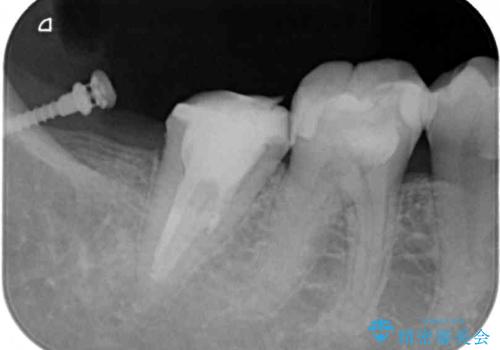

- 奥歯の詰め物が取れ、近医で再装着してもらったものの、すぐに脱落してしまったとのことで来院された患者様です。

既に神経は失活していましたが根管治療はされておらず、むし歯が大きかったためか、歯全体が手前に動いてしまっていました。

まずは根管治療を行い、その後アンカースクリューを用いて歯を適切な位置まで後方移動させた上で、セラミッククラウンによる補綴治療を行うこととしました。